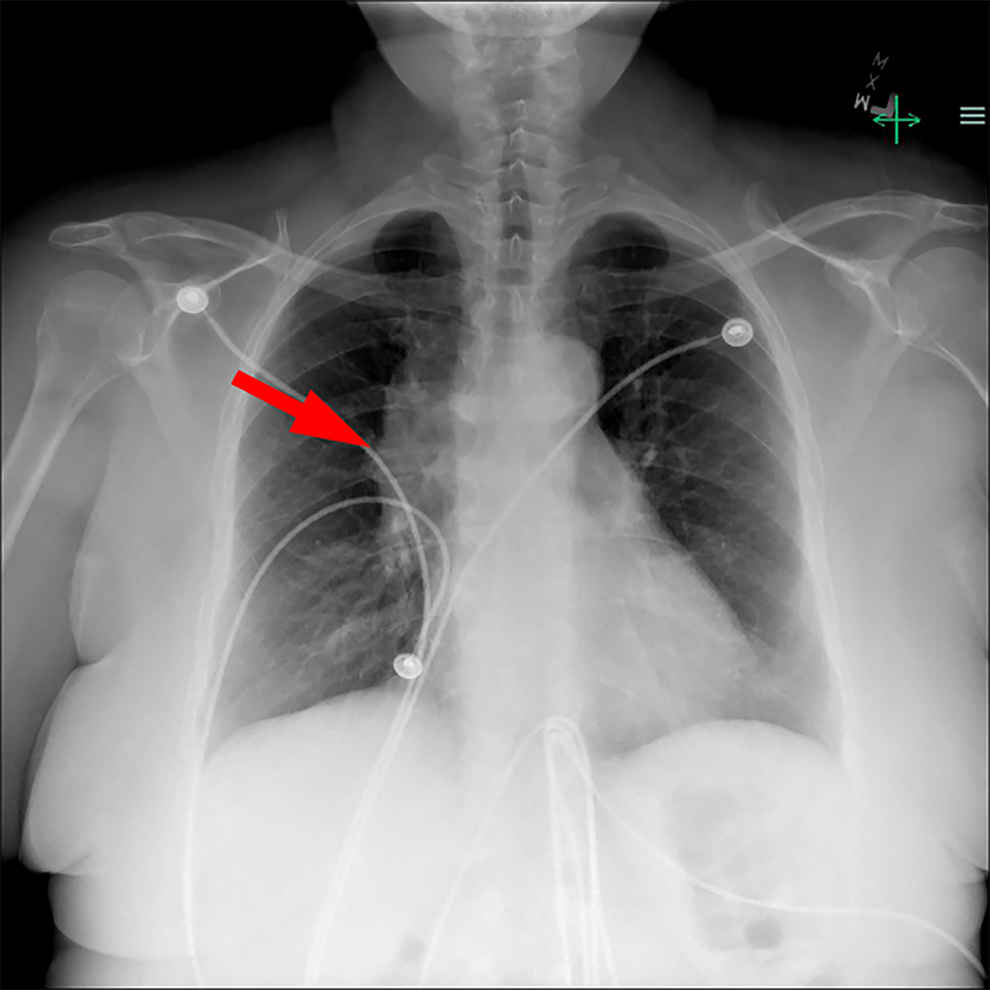

A chest radiograph is performed and shows an enlarged mediastinum suggestive of a mediastinal mass (Figure 1). Based on these findings, a magnetic resonance imaging scan of the chest is performed, which confirms an anterior mediastinal mass (Figure 2). The mass is well-defined without invasion of surrounding structures and does not show areas of hemorrhage, necrosis, calcification, or cystic change.

Chest radiography shows an enlarged mediastinal shadow on the right (arrow), suggesting a mediastinal mass.